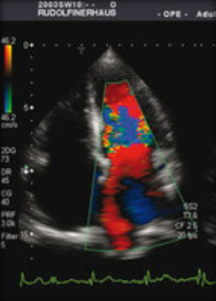

При этом мы применяем самые разнообразные методики, начиная с ЭКГ, продолжая ЭКГ с суточным (холтеровским) мониторированием, круглосуточным мониторингом артериального давления, трансторакальной и трансэзофагиальной эхокардиографией и заканчивая ультразвуковым обследованием сосудов. В дополнение к этому некоторые из наших отделений оснащены оборудованием для телеметрического контроля.